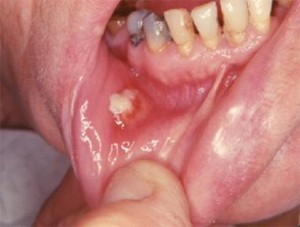

Клиническая картина. Как правило, возникает очаг уплотнения, плотный, малоболезненный. При вовлечении жевательных мышц развивается их контрактура. Кожа над инфильтратом приобретает цианотическую окраску. Различают кожную, подкожную, подслизистую, слизистую, подкожно-межмышечную (глубокую) формы актиномикоза, одонтогенную актиномикозную гранулему, поражение слюнных желез, лимфатических узлов, языка, периоста, костей челюсти, органов полости рта.

Наиболее частой локализацией являются поднижнечелюстная область, область угла и ветви нижней челюсти, шея. Течение процесса хроническое с периодическим обострением в различных отделах инфильтрата с повышением температуры тела до 38-38,5° С, усилением болей, общего недомогания. После разрешения обострения, возникновения свищевого хода или оперативного вскрытия очага острота течения исчезает. Отсутствие своевременного лечения может привести к миграции лучистого гриба через верхнечелюстную пазуху в полость черепа и появлению менингита. Распространение по клеточным пространствам шеи может осложниться медиастинитом.